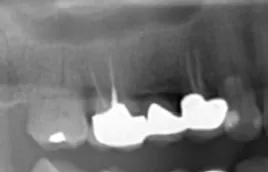

At North Balwyn Family Dental, we offer a comprehensive array of dental services that include root canal treatment to save badly damaged teeth from infections. With the utilisation of cutting-edge 3D scanning and surgical technology, our experienced dental practitioners perform the procedure with exceptional attention to detail.

Tooth decay is a painful and frustrating dental issue that demands immediate attention. Timely treatment is important to prevent bacterial infections that can severely harm nearby gum tissue and cause discomfort. Root canal treatment is a preferred solution that maintains both the appearance and function of the affected tooth, by removing infected pulp and preventing complications like tooth loss and difficulty with chewing and speaking.